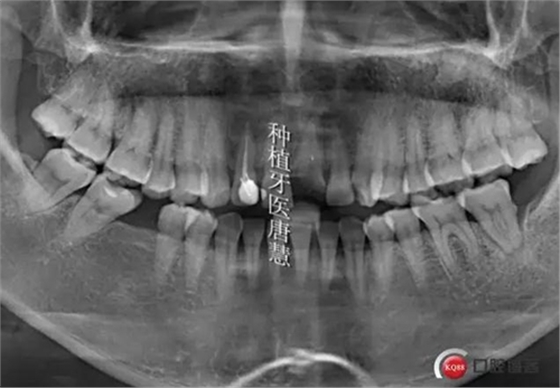

術(shù)前曲斷